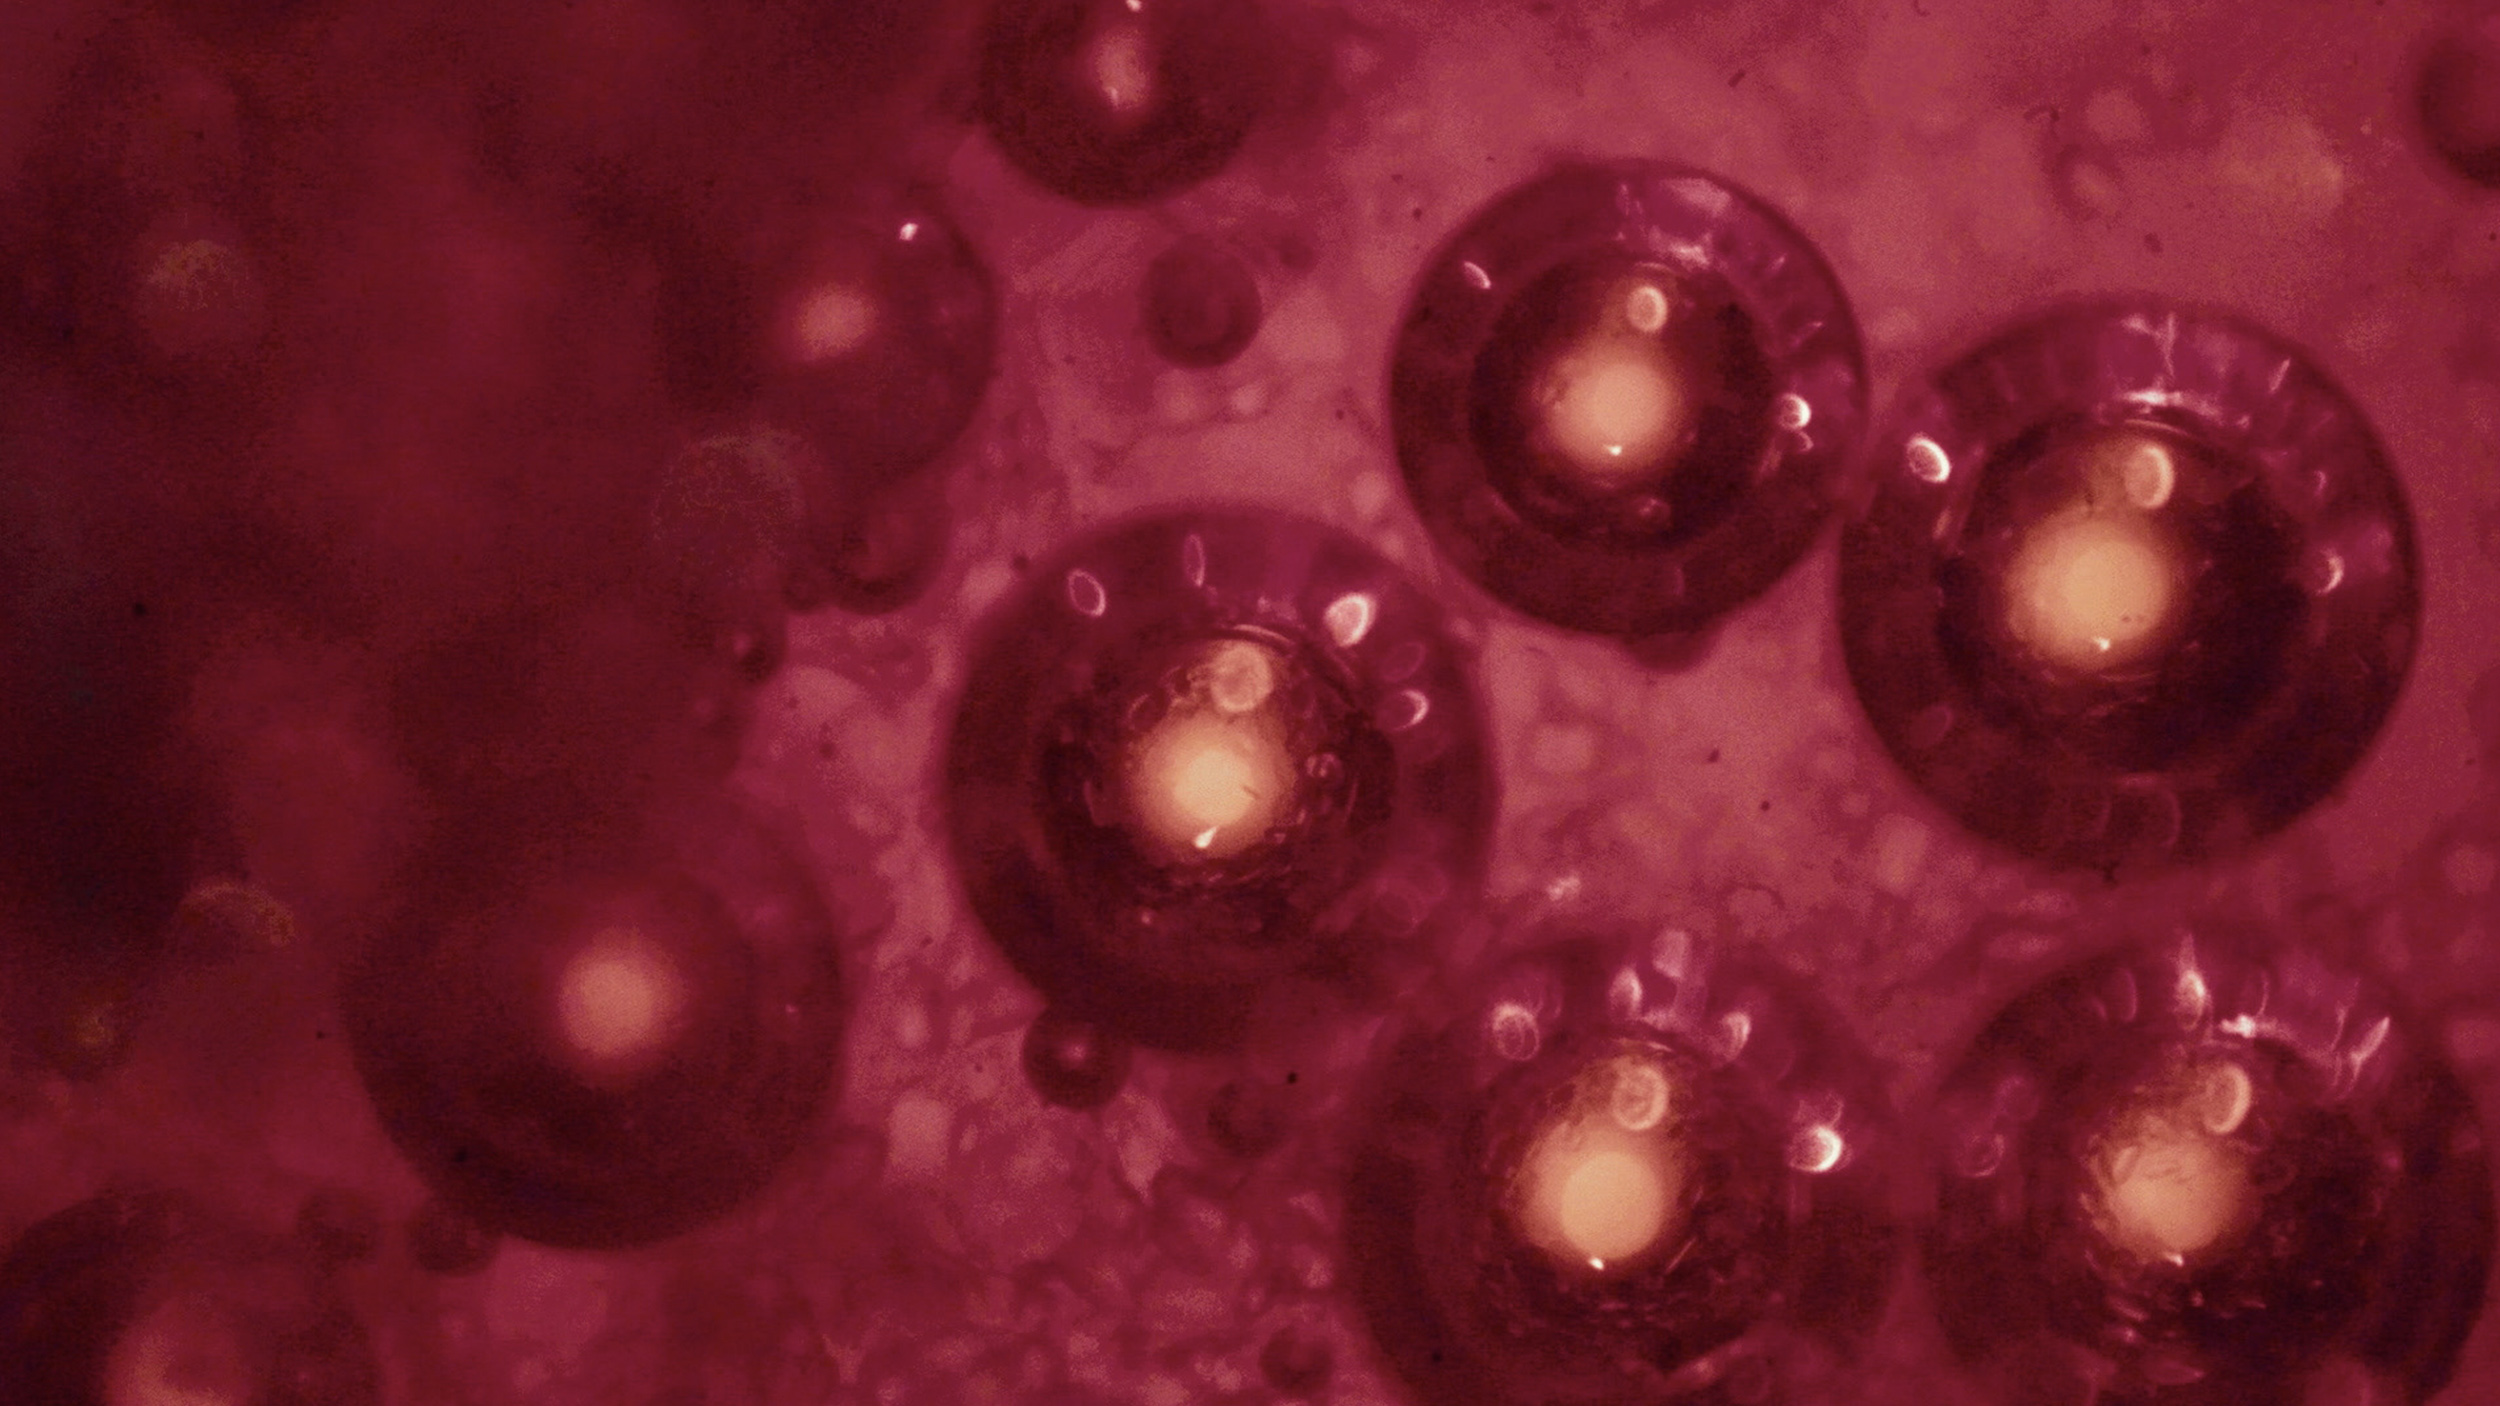

(Getty images)